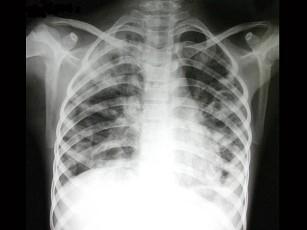

问题 男,5岁,高热、畏寒、咳嗽、胸痛1周,如图所示,最可能的诊断为?(?)

选项 A.先天性肺囊肿 B.继发型肺结核 C.支原体肺炎 D.过敏性肺炎 E.金葡菌肺炎

答案 E